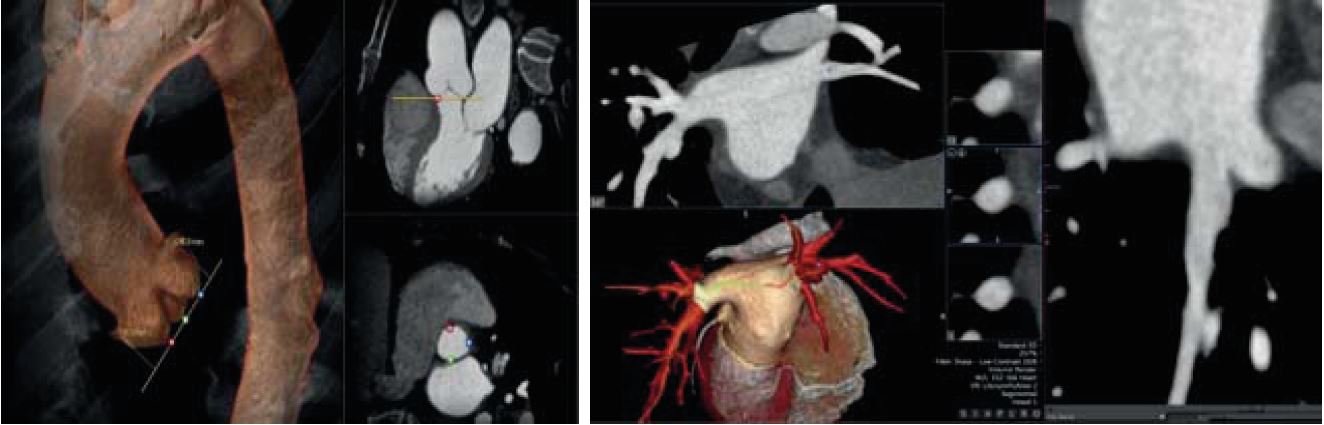

CT Transcatheter Aortic Valve Replacement (TAVR) Planning

CT Planning

Детальне передпроцедурне планування, включно з додатками, які допоможуть вам під час процедур при структурних захворюваннях серця або ЕФІ інтервенцій.